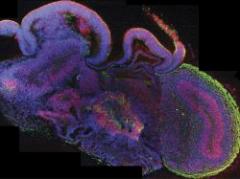

Un equipo de cientÃficos europeos ha desarrollado pequeños cerebros humanos tridimensionales, de cuatro milÃmetros de diámetro, a partir de células madre pluripotentes que ayudarán a profundizar en el estudio de las enfermedades neurológicas, informó este miércoles la revista cientÃfica "Nature".ver más